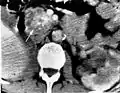

Pancreatic serous cystadenoma | |

![]() | |

Micrograph showing a pancreatic serous cystadenoma. H&E stain. | |

Pancreatic serous cystadenoma is a benign tumour of the pancreas.[2] It is usually solitary and found in the body or tail of the pancreas, and may be associated with von Hippel–Lindau syndrome.[2]